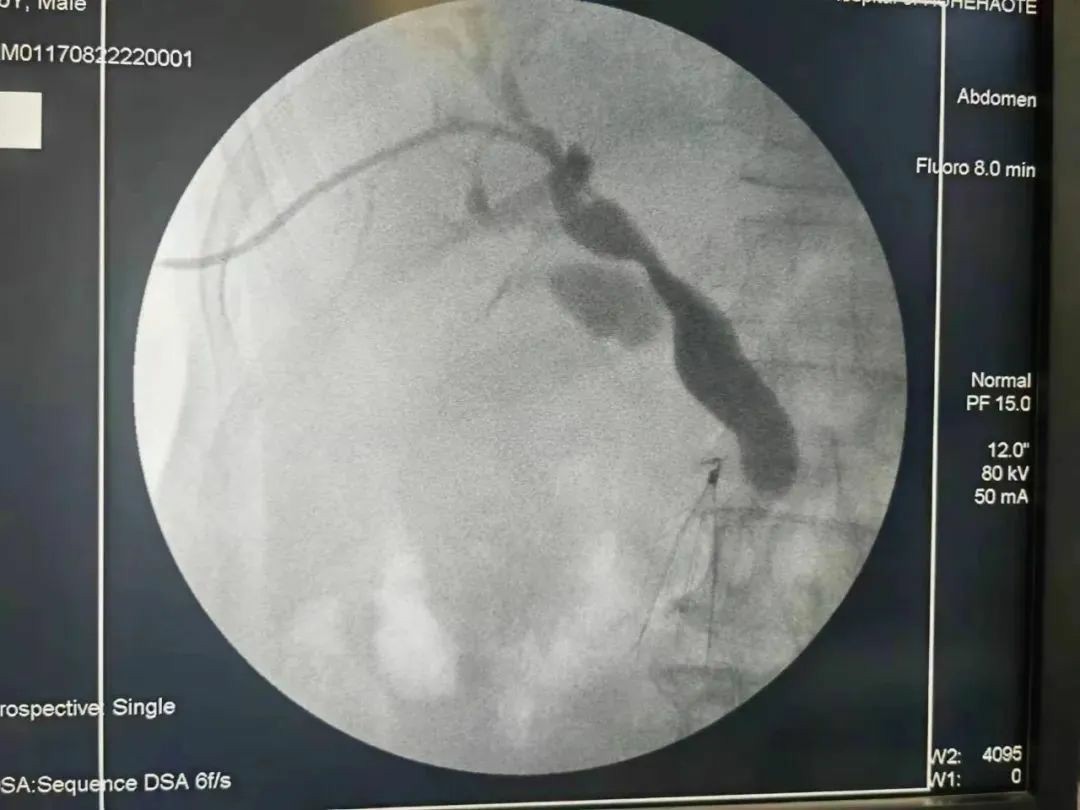

这位退伍老军人,66岁,2周前出现周身无力,不想吃饭,并间断伴有恶心、呕吐,近1周又开始出现皮肤瘙痒,症状逐渐加重。患者儿子在网上查到袁春旺主任医师到呼市二院挂职副院长后第一时间预约袁春旺副院长的专家号,并带着老父亲如约就诊。袁春旺副院长详细询问病情,细致查体,还不忘向跟诊学习的年轻医师讲解:像这种皮肤、眼巩膜逐渐变黄伴皮肤瘙痒,就是老百姓所说的“小金人”,这种情况大概率是胆道梗阻,原因有良恶性之分,这需要进一步检查加以明确,病因明确后需要尽早减黄治疗。当天患者即被收入该院中西医结合肝病肿瘤介入科,入院后检查总胆红素已经高达809umol/L,以直接胆红素升高为主,腹部增强核磁提示肝内外胆管及胆囊均明显扩张,胰管形态良好,未见明显扩张,考虑胆管末端占位可能。袁春旺组织多学科会诊,联合会诊意见:患者老年男性,黄疸增长迅速,肝功能损害严重,不及时处理肝衰竭危险高,首先应尽快减低黄疸。经与患者家属充分沟通后,家属同意行DSA引导经皮肝穿刺胆道引流术。于是就有了上面的成功微创介入手术。